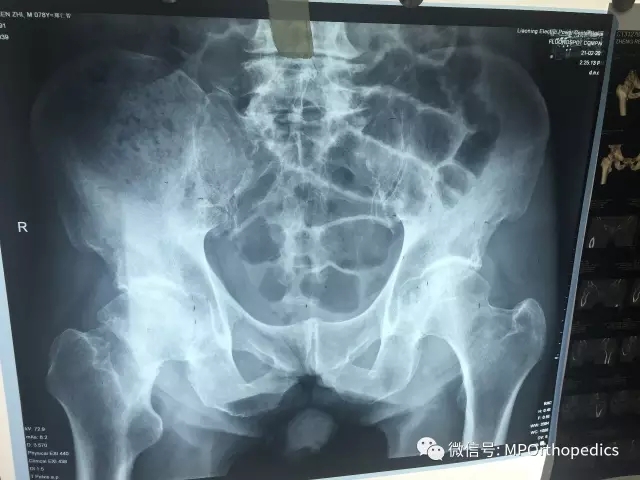

本次受益于此手术的患者是78岁右侧股骨颈骨折的男性病人,侯德才主任术前综合评估患者情况后,详细规划好术前计划,术中采用的SuperPath TM入路(5.5cm切口),经由梨状肌,臀小肌间隙入路,借助经皮穿刺套管完成髋臼的骨准备及人工关节组建的安装,术中不切断任何肌肉组织和肌腱,完整的保留了短外旋肌群,且缝合复原关节囊,大大降低了病人术后髋关节后脱位的风险。病人麻醉苏醒后能早期下床进行全范围的功能锻炼。

术前X光片